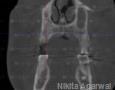

CBCT :

Yes

Pictures

Baseline